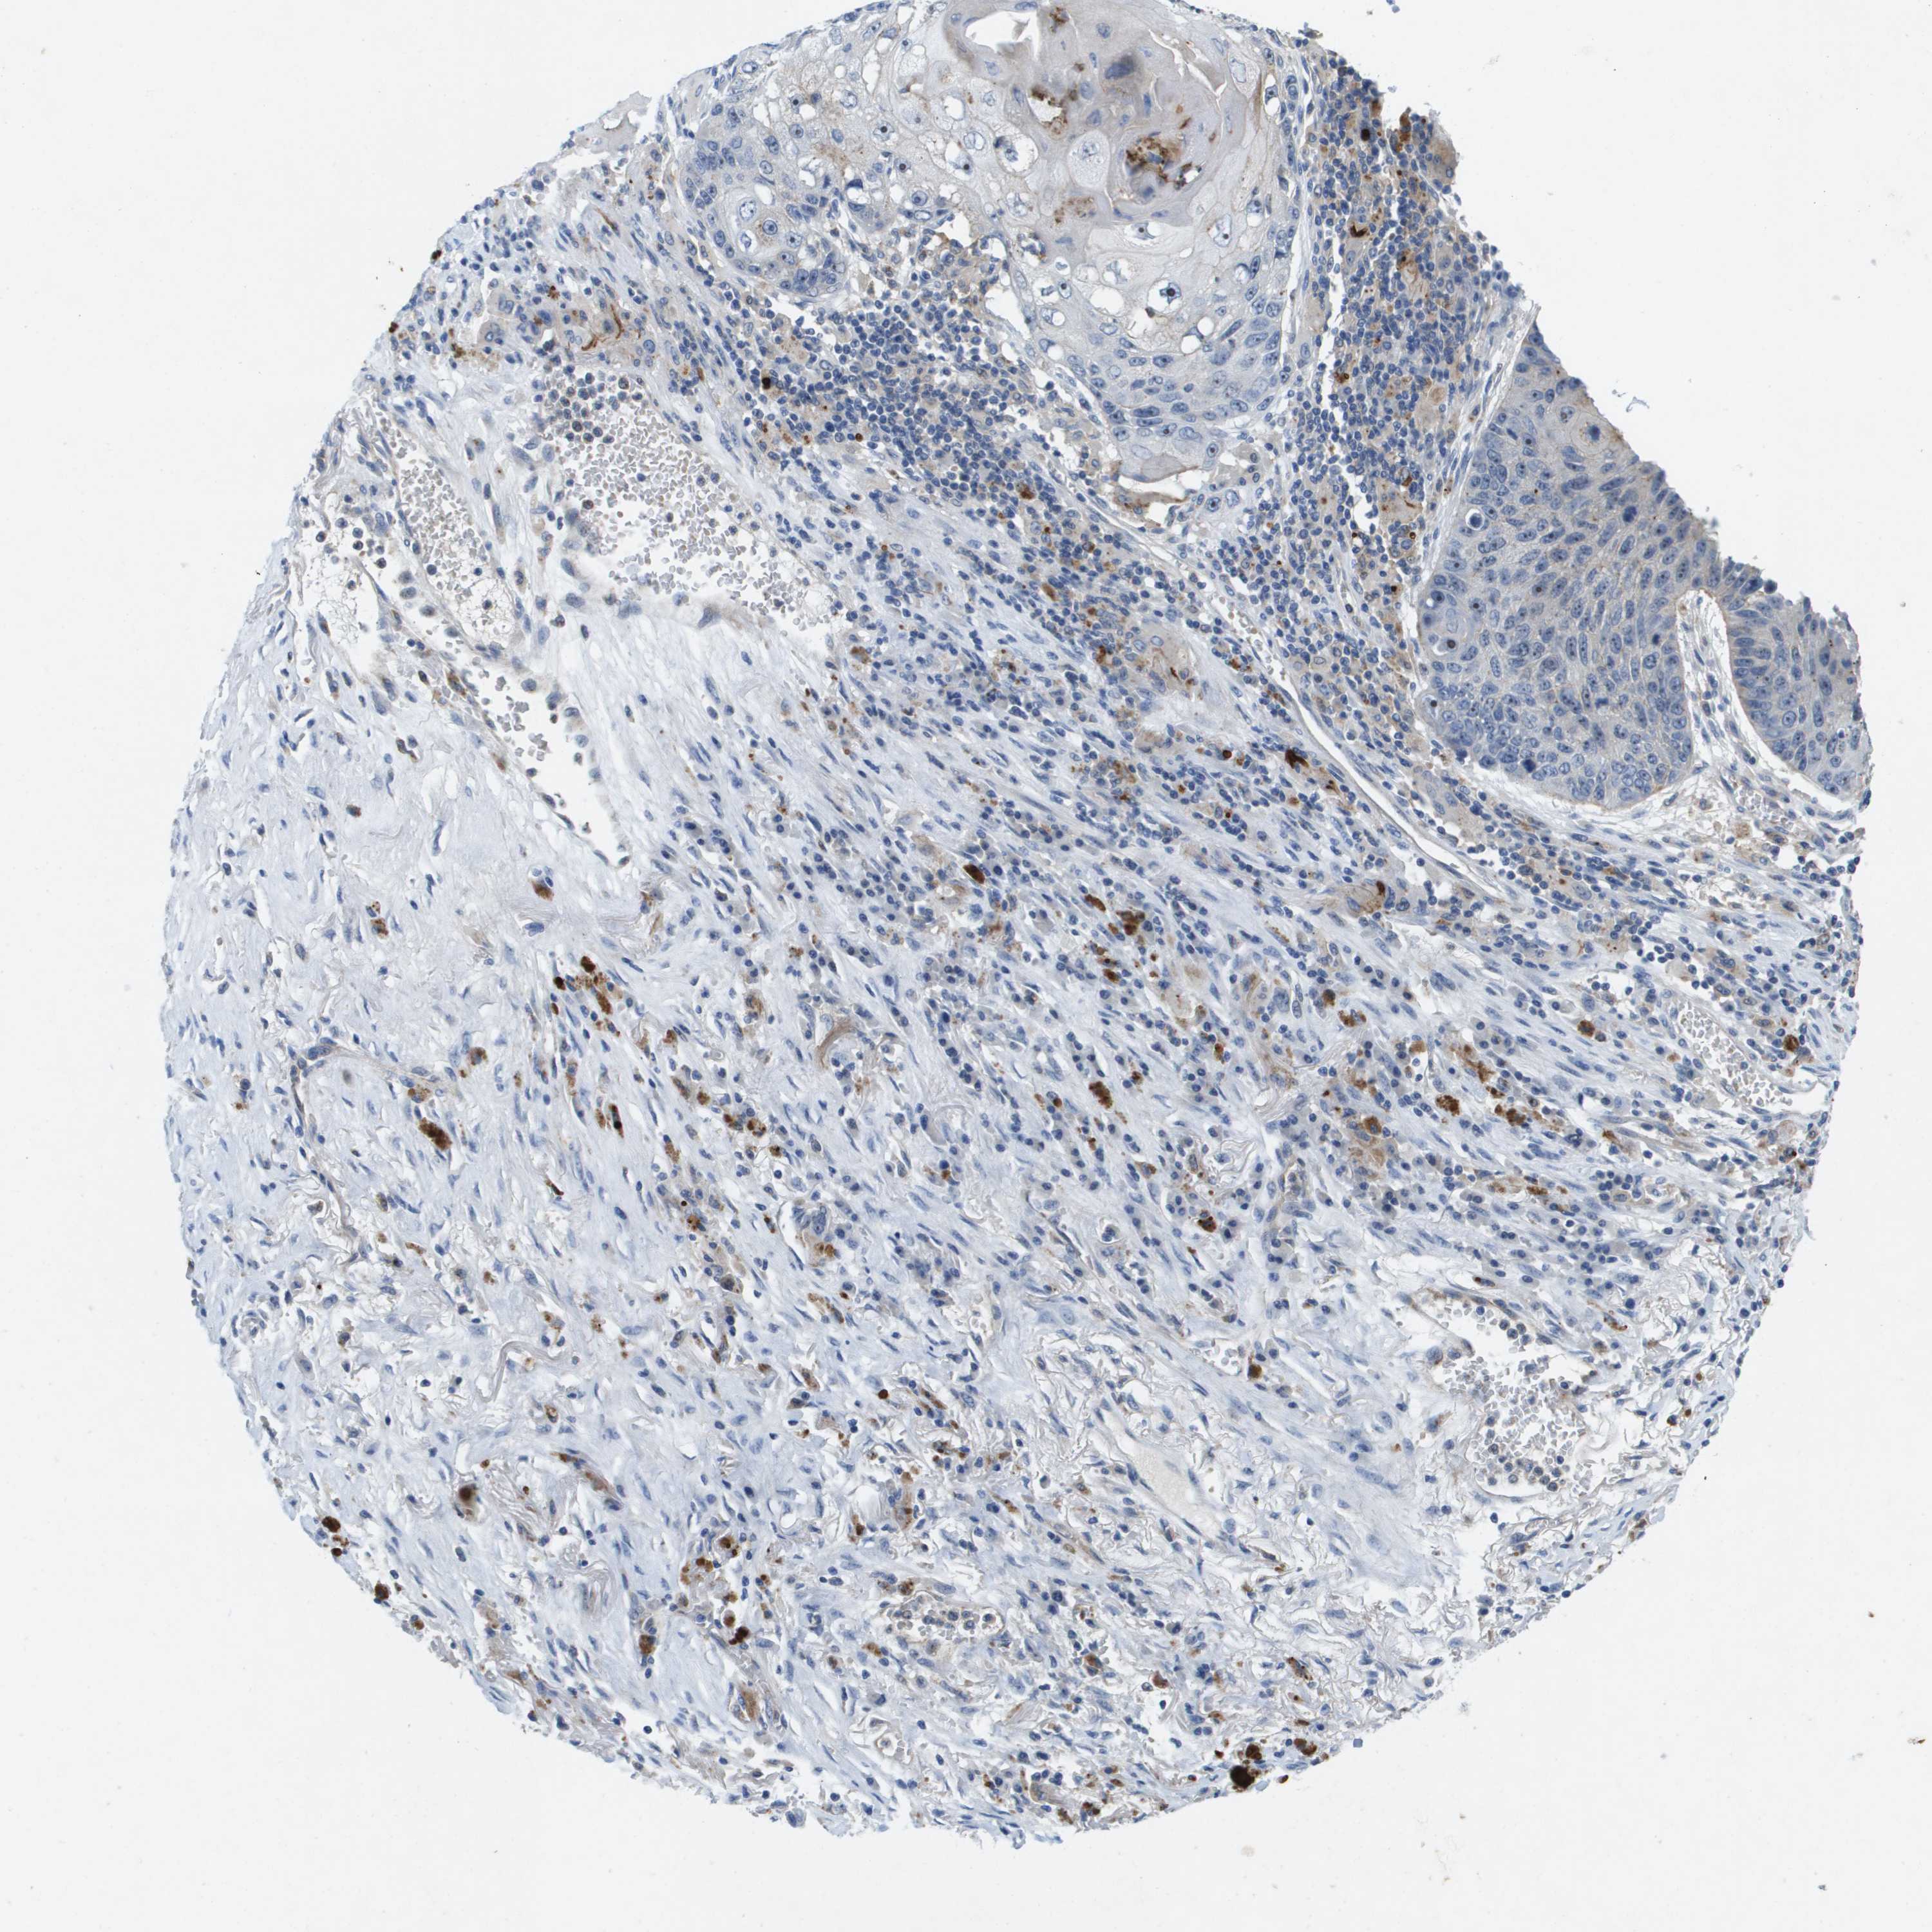

CANCER LUNG CANCER Show tissue menu

LUAD TCGA LUAD VALIDATION LUSC TCGA LUSC VALIDATION PROTEIN LUAD CPTAC PROTEIN LUSC CPTAC PROTEIN EXPRESSION

ANTIBODIES

AND

VALIDATION